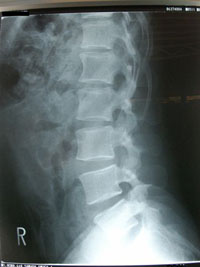

ヘルニアは飛び出るという意味ですのでレントゲンでそれらしい状態が映っていたり、MRIでみつけることができ画像診断が行われます。

脊柱間狭窄症は、その神経が通っている脊柱管が、靭帯や骨、関節、椎間板が老化して形が変わったために狭くなり、神経根や脊髄神経が圧迫されて痛みを感じる病気です。

一般的な原因としては、加齢により椎間板が変形して大きくなってはみ出たり、骨が変形して脊柱管が狭くなることが多いようです。